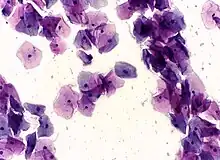

![]() High-grade squamous intraepithelial lesion | |

Micrograph of a normal pap smear